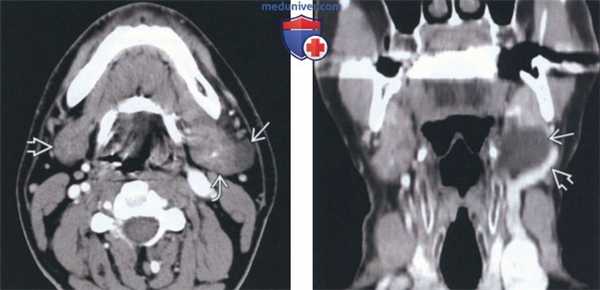

(Слева) На аксиальной КТ с КУ определяется овальное гиподенсное образование, заполненное жидкостью, исходящее из задних отделов левой поднижнечелюстной железы и не отделенное от нее. Правая поднижнечелюстная железа не изменена.

(Справа) На сагиттальной КТ с КУ у этого же пациента визуализируется мукоцеле, выбухающее со стороны заднего края поднижнечелюстной железы. Обратите внимание на левую лицевую вену, лежащую параллельно наружному краю мукоцеле, что позволяет исключить кистозный поднижнечелюстной лимфоузел.

(Слева) На аксиальной КТ с КУ левая поднижнечелюстная железа выглядит нетипично. Визуализируется эксцентрический гиподенсный участок, неотделимый от железы, которая лишь слегка увеличена по сравнению с поднижнечелюстной железой справа. Проток не расширен.

(Справа) На корональной КТ с КУ определяется типичный случай мукоцеле поднижнечелюстной железы. Визуализируется овальное образование с плотностью жидкости. Обратите внимание на лицевую вену, огибающую наружный край образования.